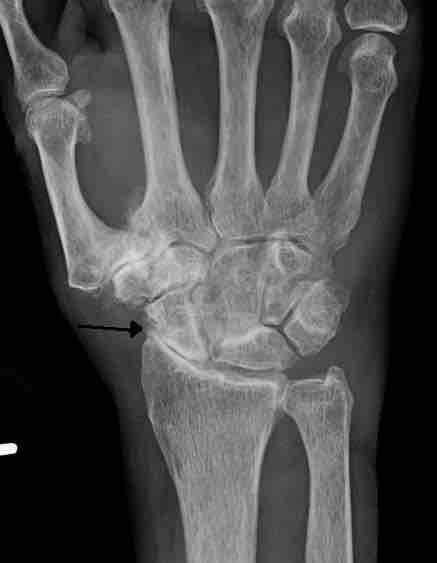

Severe osteoarthritis and osteopenia of the carpal joint and first carpometacarpal joint.